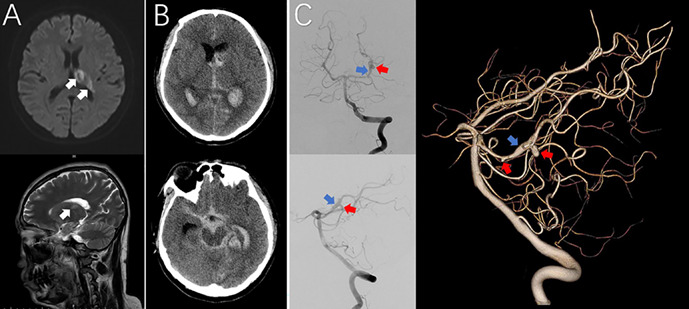

Clinical Images: Active neuro-Behçet's disease manifesting as cerebral aneurysm rupture after acute cerebral infarction.

临床表现:活动性神经behaperet病表现为急性脑梗死后脑动脉瘤破裂。